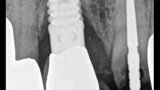

Fig. 18: A periapical radiograph

with a drill in place confirmed that the apex length had been reached and that all the gutta-percha had been removed.